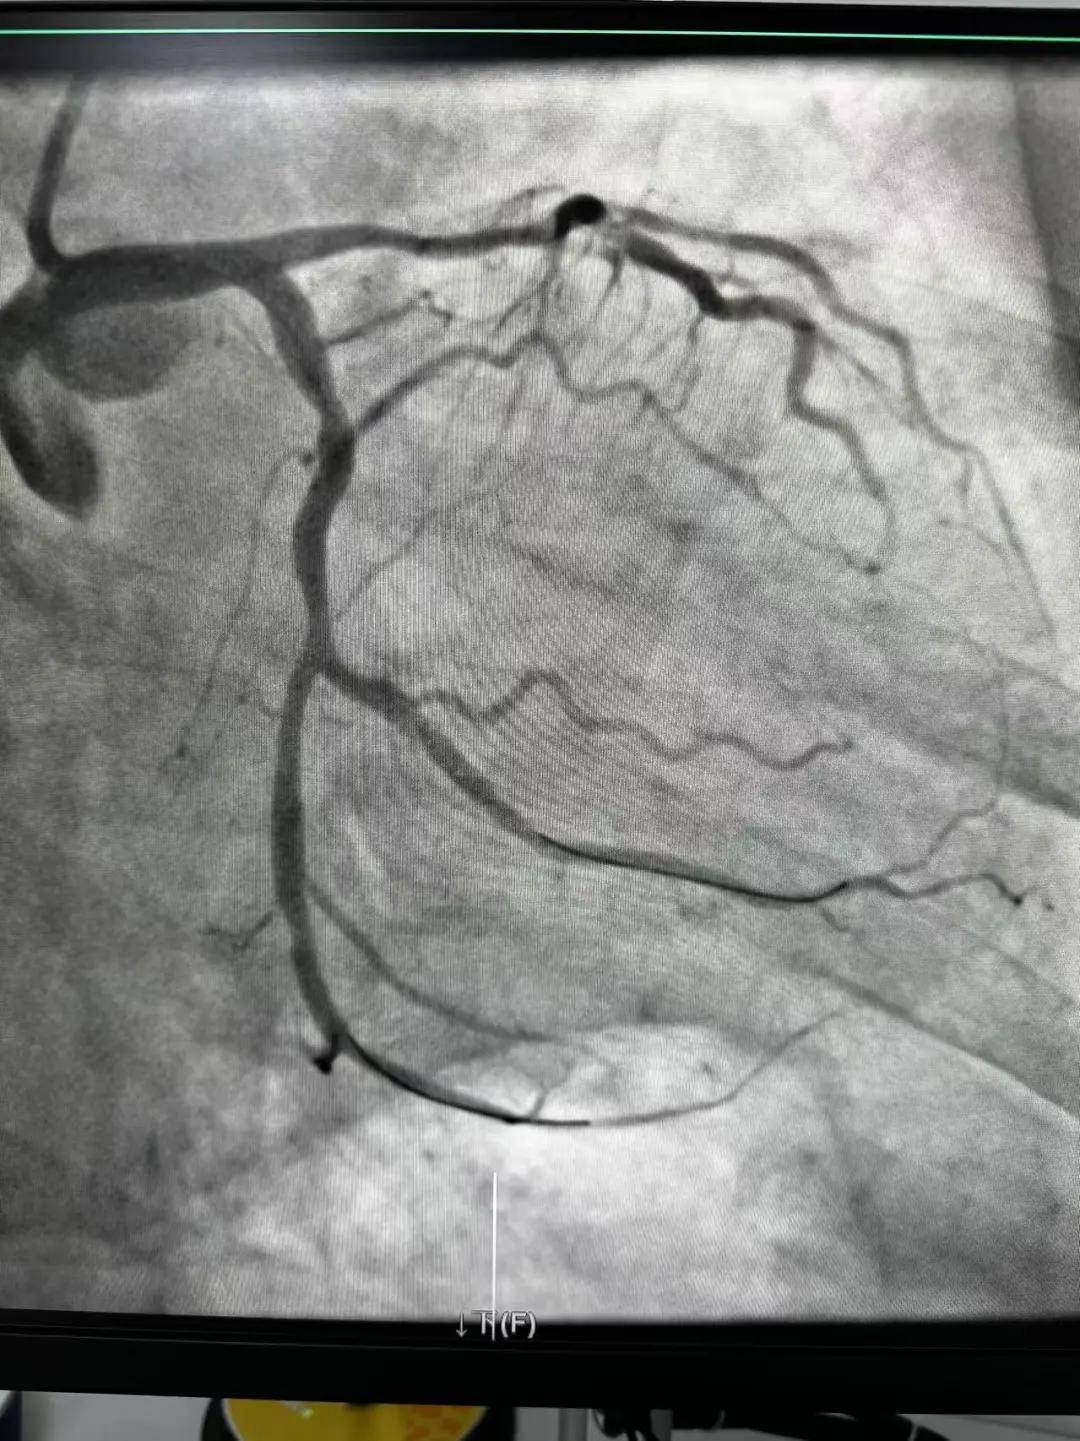

今天最后一臺手術(shù),是一個嚴(yán)重三支病變的病人,患者張大爺,71歲,以“突發(fā)胸悶胸痛3小時”為主訴入院。經(jīng)心電圖檢查后示室上性心動過速,以“冠心病、心絞痛、心律失常”為診斷收住入心內(nèi)科。心內(nèi)科團(tuán)隊通過審慎評估,決定給予患者冠狀動脈造影術(shù)及冠狀動脈內(nèi)支架置入術(shù)。

手術(shù)開臺,在王云峰主任的帶領(lǐng)下,心內(nèi)科團(tuán)隊為張大爺進(jìn)行穿刺。由于病人重聽,在手術(shù)臺上配合度不高,加上病情嚴(yán)重,導(dǎo)致手術(shù)難度加大。手術(shù)正在緊張進(jìn)行中,導(dǎo)管室內(nèi)線電話又急促響起!一位急性心肌梗死患者情況危急,需要緊急進(jìn)行介入治療。

許先生,52歲,大貨司機(jī),在鶴壁至安陽卸貨過程中,突發(fā)胸悶胸痛,伴大汗1.5小時。 患者繞行安陽,于11點38分到達(dá)我院大門,11點41分首份心電圖,提示患者下壁心肌梗死。 起病急,病程短,情況十分危險,如果血管完全堵塞將直接威脅患者生命,亟需疏通堵塞血管進(jìn)行血運(yùn)重建。

時間就是生命,時間就是心肌,救治刻不容緩。王云峰主任立即啟用第二個手術(shù)間進(jìn)行“雙開臺”!將現(xiàn)有人員兵分兩路,兩路人馬各司其職,兩條救心“高速路”為患者火速同時搭建起來。副院長趙清亮也趕到導(dǎo)管室,親自坐鎮(zhèn)指揮。

穿刺、造影、放支架……兩個手術(shù)間各個環(huán)節(jié)緊張卻有序地進(jìn)行著!在心內(nèi)科團(tuán)隊精準(zhǔn)、默契的配合下,兩臺手術(shù)順利完成! 兩名患者的快速、同時、成功救治,得益于殷都區(qū)人民醫(yī)院醫(yī)務(wù)人員快速的應(yīng)急能力、過硬的急救技能,同時更得益于導(dǎo)管室同開臺,保障了救治的迅速有效。